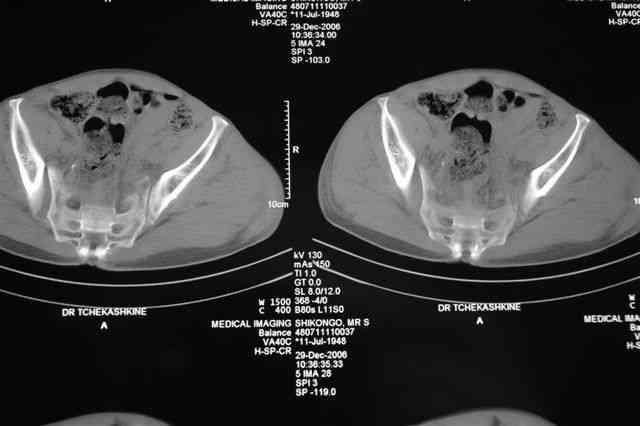

Я помню технику транссакральной фиксации тазового кольца длинными 5 мм Шанцами - повреждения типа В, в этом же случае задний отдел тоже вовлечен

т.е комбинированная нестабильность, поэтому вопрос - достаточно ли только двух Шанцев для стабилизации таза? Что вы думаете об anterior Right SI joint plating + tension band plating from the back.?

Элегантная фиксация, поздравляю.Но ваш случай : одноплоскостная горизонтальная нестабильность Tyle B2.2 отличен от представленного мной - у

моего больного + вертикальная нестабильность за счет повреждения правого крестцово-подвздошного сочленения и перелома заднего отдела подвздошной

кости- С2 тип. Поэтому и возникла дилемма : выбор оптимальной фиксации заднего отдела:

По-поводу фиксации таза спонгиозными винтами. Данный способ все-таки показан для фиксации повреждения крестцово-подвздошного сочленения или переломов крестца. Мне кажется, что в данной случае ситуация иная - имеется перелом "основания" крыла подвздошной кости (в который вовлечена и поверхность, составляющая крестцово-подвздошное сочленение). Не уверен, что фиксация данного повреждения (и заднего полукольца) винтами будет стабильной, так как именно на уровне 1-2 крестцовых позвонков (где обычно вводят винты) линия перелома уходит в латеральном направлении от крестцово-подвздошного сочленения.

PI>По-поводу фиксации таза спонгиозными винтами. Данный способ все-таки показан

для фиксации повреждения крестцово-подвздошного сочленения или переломов крестца. Мне кажется, что в данной случае ситуация иная - имеется перелом

"основания" крыла подвздошной кости (в который вовлечена и поверхность, составляющая крестцово-подвздошное сочленение). Не уверен, что фиксация данного повреждения (и заднего полукольца) винтами будет стабильной, так как

именно на уровне 1-2 крестцовых позвонков (где обычно вводят винты) линия перелома уходит в

латеральном направлении от крестцово-подвздошного сочленения.

Я просмотрел томограммы и у меня создалось впечатление, что винтам есть за что *зацепиться*. В сочетании с 5 мм Шанц винтами, проведенными через нижне-переднюю ость спереди назад через КП сочленения -стабильность тазового кольца должна восстановиться. - Это , конечно, при условии , что закрытая рнепозиция будет успешной.

после КТ отказался от этой идеи - двусторонний перелом крестца в зоне 1 - алярная часть, при попытке низведения правого гемипелвиса теоретически есть вероятность смещения

фрагмента крестца слева.

Закрытая фиксация задних отделов илиосакральными винтами, как представляется, не оптимальна по двум причинам: во-первых, не устранено вертикальное смещение (через 3 нед тракцией это вряд ли удастся), во-вторых, велика вероятность попасть в линию перелома.